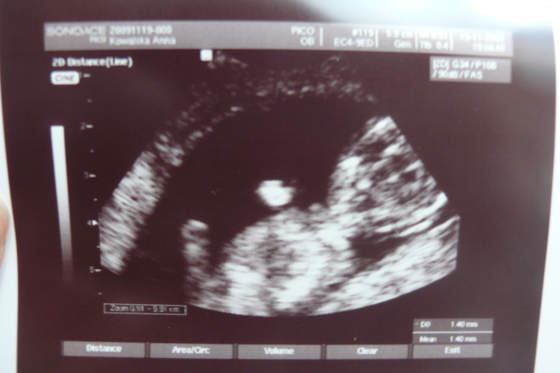

Nasze fasolki na USG

Nowy obraz3.jpgUSG z 12 tygodnia 4 dnia czyli z wczoraj :)